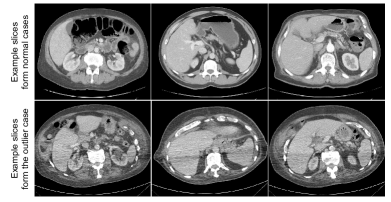

Refer to caption

Figure 9: Illustration of example CT slices from general cases and an outlier case with artefacts, in the task of multi-organ segmentation in abdominal data.

We have conducted case study regarding an outlier case with image artefacts in the abdominal CT dataset. As illustrated in Fig. 9, the outlier case presents clear artefacts with worse image quality compared with other general cases, noting that all the training cases are good-quality images without artefacts. The mean results of the four abdominal organs using seven different settings are listed in Table VI, where we see that all comparison methods obtained a lower performance on this one case (compared with general results in Table II). Our approach achieved a higher Dice score with a smaller Hausdorff distance compared with the other methods, demonstrating our superior robustness at lower image quality.